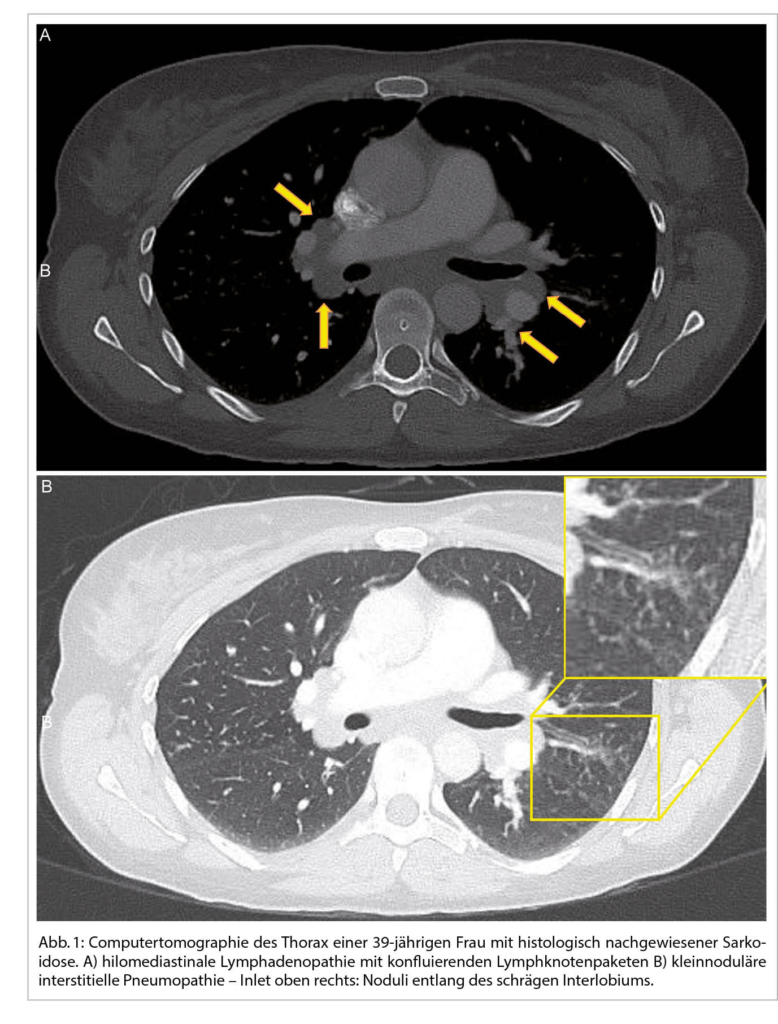

Bei einer typischen Präsentation eines Löfgren-Syndromes kann auf eine bioptische Diagnosesicherung verzichtet werden. Im Normalfall wird die Diagnose durch den Nachweis von epitheloidzelligen Granulomen und Auschluss einer anderen granulomatösen Erkrankung gestellt. So muss im Ausschlussverfahren das Vorliegen einer infektiösen Erkankung (vor allem Tuberkulose, Pilzinfekte), einer «sarkoid-like» Reaktion assoziiert mit malignen Erkrankungen, sowie unter weiteren einer Berylliose ausgeschlossen werden. Da in den meisten Fällen die Lunge betroffen ist, kommt der Bronchoskopie als sicheres und minimal-invasives Verfahren eine wichtige Rolle zu. Bei der Bronchoskopie kann eine Gewebeprobe asserviert und eine broncho-alveoläre Lavage durchgeführt werden. Bei einem extrapulmonalen Befall entscheidet häufig die Zugänglichkeit einer Gewebeprobe über die Durchführung des geeigneten Diagnoseverfahrens. Zudem ist initial ein Organscreening indiziert, um eine subklinische Organbeteiligung erfassen zu können. Hierfür wird eine ophtalmologische Untersuchung, ein Abdomenultraschall und eine kardiologische Beurteilung mit EKG, transthorakaler Echokardiographie und 24 h-EKG empfohlen. Die Labordiagnostik umfasst Differential­blutbild, Leber- (AP, γGT) und Nieren- (Kreatinin, GFR) Tests, Serumkalzium sowie eine Bestimmung der angiotensin-converting enzyme (ACE) und löslichen IL-2-Rezeptor alpha (sIL-2Rα). Dazu folgt eine Urinanalyse mit Kalziumspiegel und Sediment sowie eine fraktionierte Kalzium-Ausscheidung. Die radiologische Klassifikation nach John Scadding ist immer noch in Gebrauch und hat einen prognostischen Wert. Eine funktionelle Untersuchung der Lunge (Spirometrie, Bodyplethysmographie und CO-Diffusion) und eine hochauflösende Computertomographie (HRCT) sind die bevorzugten Methoden zur Beurteilung der Lungenbeteiligung und ihres Schweregrads (1). Eine Lungensarkoidose kann sowohl zu restriktiver, wie auch obstruktiver oder gemischter Ventilations­störung führen.